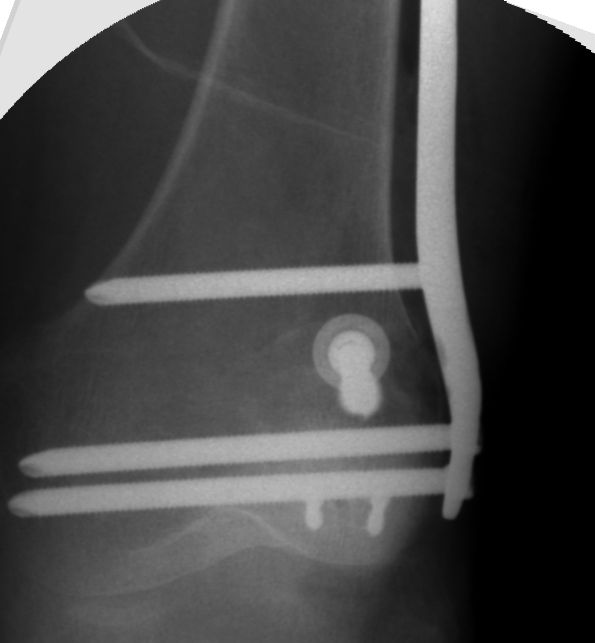

the displacement forces on the condyle are pretty huge, and even NWB, any valgus knee stress is going to want to wreck my reduction, so the distal DCS screws were placed to not only engage and compress the fragment, but to also 'haystack' against the most distal transverse screw

This one distal posterior screw being the killer, and driving right through the meat of the fragment and scraping along the roof of the notch (crosshairs on the CT demonstrate the screw position/trajectory)

doing some funky 3D image manipulation preop - could see the overlapping window of the condyle fragment and the limit of the notch (blumensaats line)

this is the only place (meaningful) transverse screws can go

Subacute lateral Hoffa fracture

I love it when you step back to look at the imaging following an case - and the result ends up being some utterly minimalistic yet biomechanically elegant solution.

Every single screw has a single simple purpose, yet the big picture is a construct which locks together